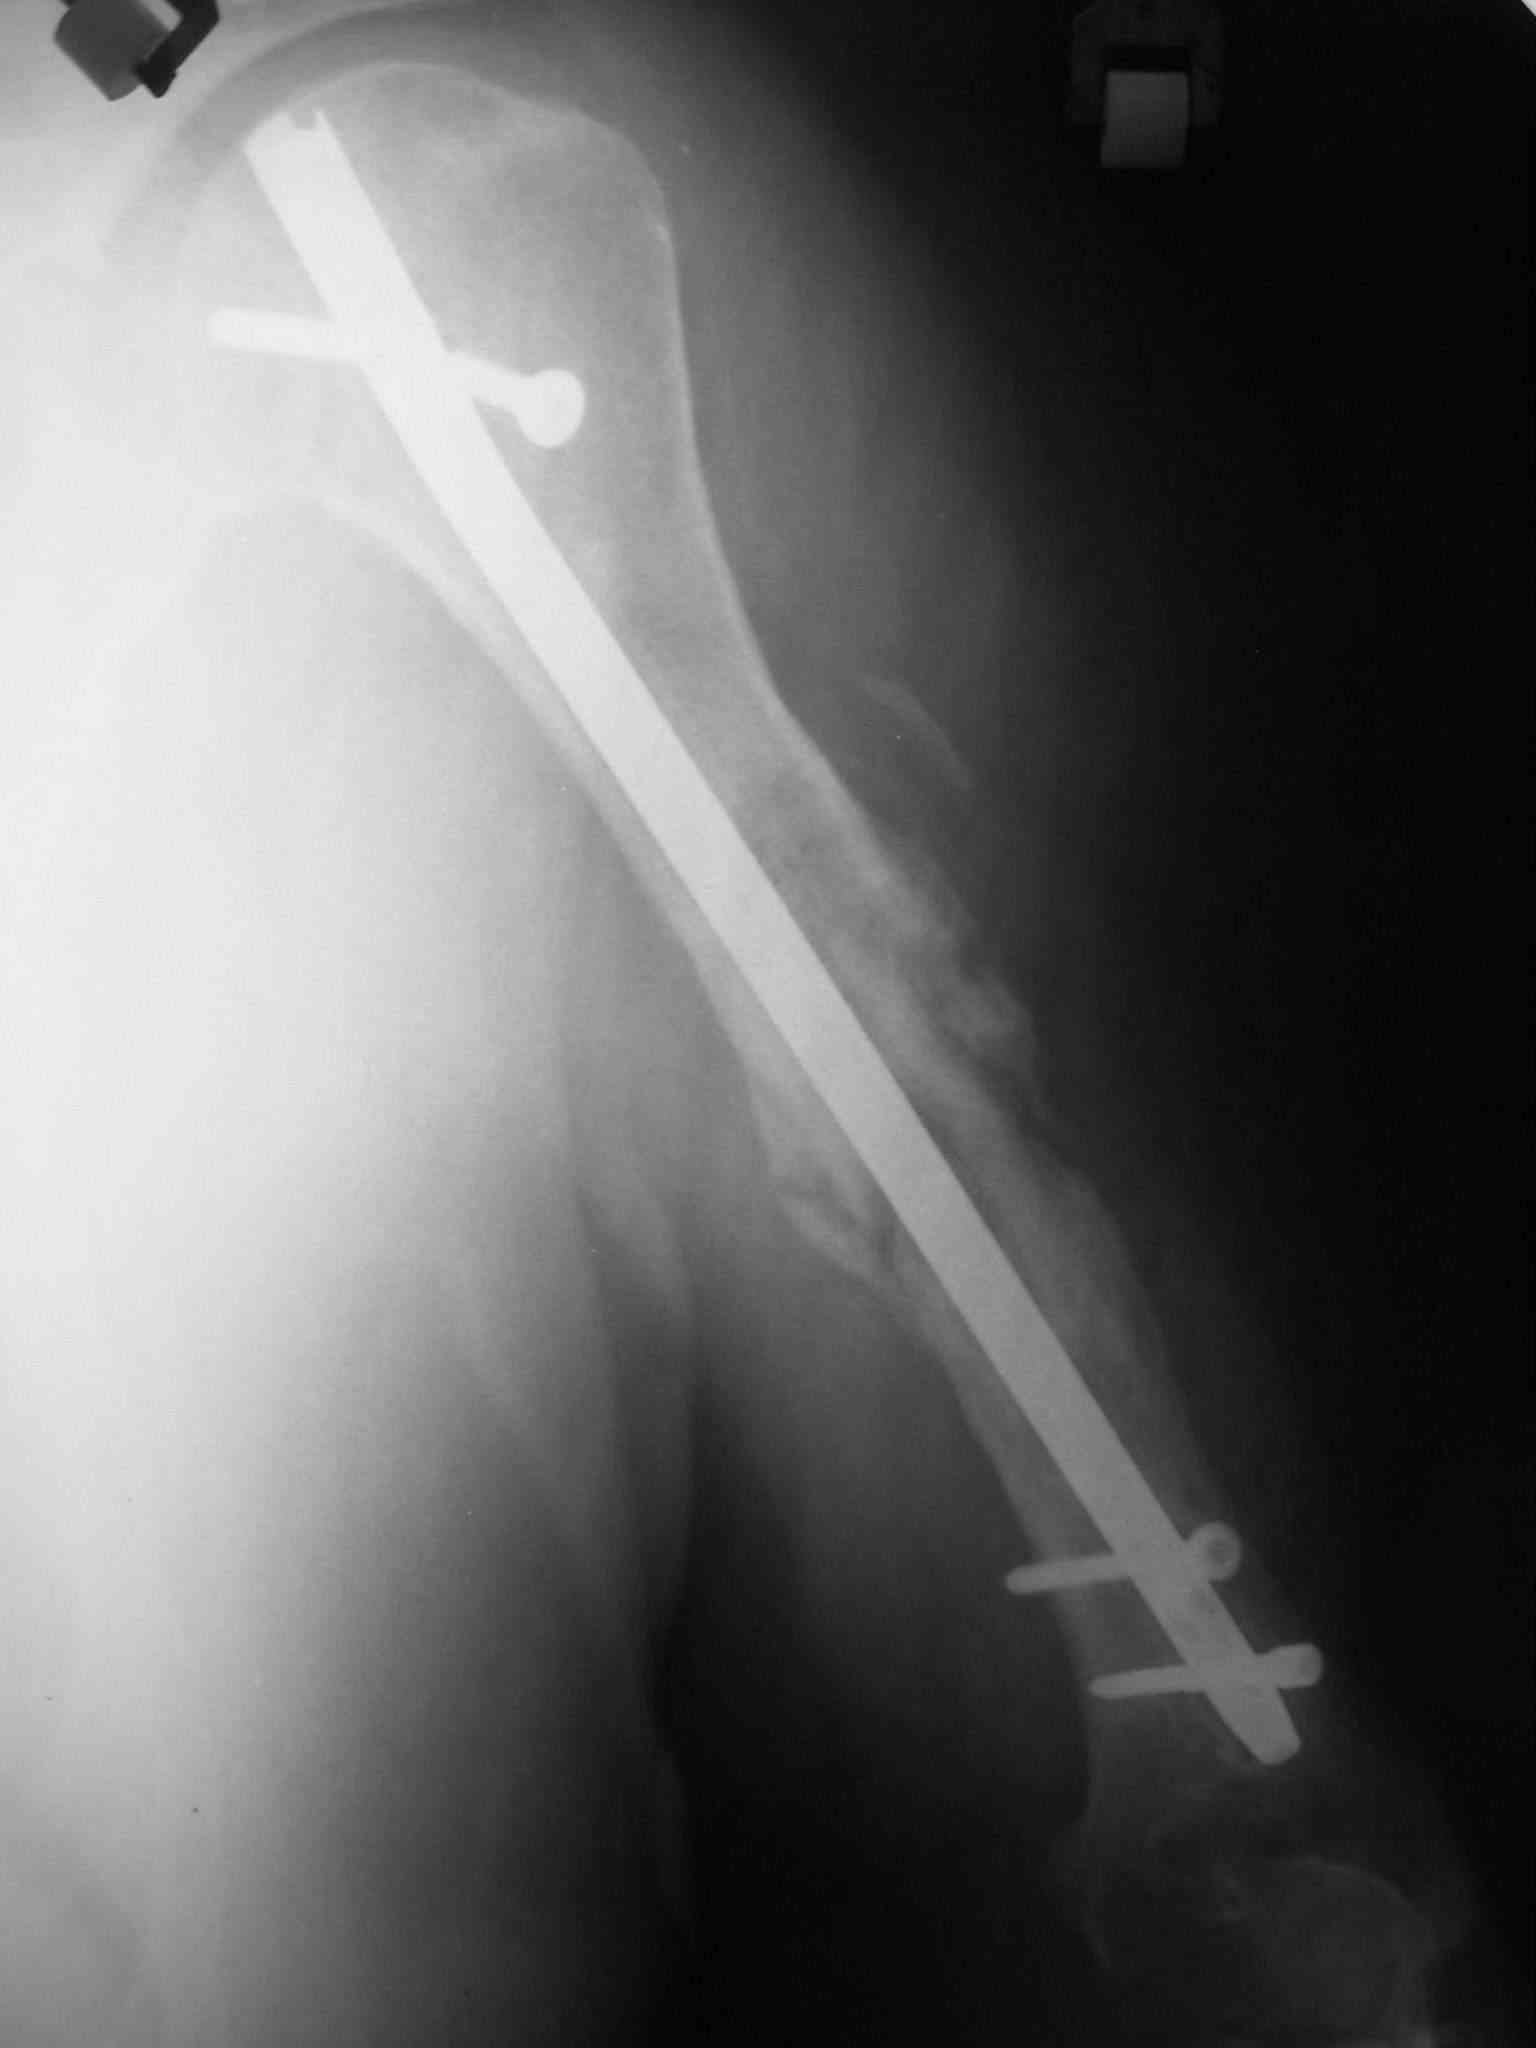

Объективно очевиден лишь тот факт, что не смотря на варианты фиксации перелом несрося за 1.5 года, и по снимку речь вряд ли идет о рефрактуре. Отрицать предположение А.Н.Челнокова о дремлющей инфекции при отсутсвии объективных методов исследования более чем не обосновано. Риск септического воспаления выше чем при первичном остеосинтезе, поэтому выбран более надежный препарат профилактики.

Откуда возникли сомнения в качестве фикс атора? Речь идет о штифтах Chm, просто стальные 7мм неканюлированы, 8 и 9мм - полые, а титановых нет в наличии(в производстве Chm). Вопрос в том - ставить с плотной посадкой и широким рассверливанием 8-9мм или же, учитывая риск инфекции, 7 мм сплошной?

Ну это уже хоть что-то. Вполне может, по этим снимкам показалось, что там периостальные наоения какие-то... остеомиелитно-подозрительные.

БИОС делали открыто, с декортикацией, частичным торцеванием и костной аутопластикой. Вариант БИОС - компрессирующий). Насчет компрессирующего варианта БИОС потом пожалели - проксимальный блокируемый винт сломался через год, надо было делать стабильный вариант.